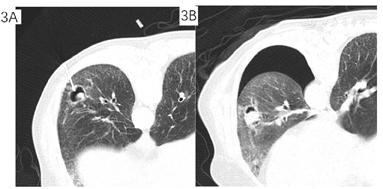

分别于2021年12月30日、2022年1月6日、2022年1月17日、2022年1月25日行4次支气管镜检查及治疗,超声探查示左下叶前基底段外侧支异常低回声,局部予乙酰半胱氨酸+生理盐水反复灌洗后,注射猪源纤维蛋白粘合剂+两性霉素B,术后咳嗽症状缓解出院。2022年3月11日于我院通州院区住院,3月12日胸部CT平扫(经支气管镜局部注药后复查),曲菌球较我院初诊缩小(图2)。于2022年3月21日行经皮穿刺注药(猪源纤维蛋白+两性霉素B),复查即刻CT示气胸,予胸腔闭式引流(图3)。2022年3月23日行微波消融治疗(图4),45 W消融3 min,复查CT示覆盖病灶,继续保留闭式引流,次日复查胸片无气胸,拔除引流管。

三、腔内注药为可选择的局部治疗策略。根据我院情况,考虑患者经皮操作出血风险,予4次气管镜下治疗,超声定位后予注药,注药策略选择猪源纤维蛋白粘合剂+两性霉素B混合物。其中猪源纤维蛋白粘合剂的作用主要为降低出血风险并使得两性霉素B缓释。两性霉素B是多烯类抗真菌药,抗真菌谱广而强,但是静脉给药时,常用治疗量所达到的药物浓度对真菌仅有抑菌作用[5]。欧洲临床微生物学与感染病学会(ESCMID)与欧洲呼吸病学会(ERS)于2015年发布的《慢性肺曲霉病诊断与治疗指南》对于局部注药剂量和溶液浓度的相关规定进行了说明[6],相关临床报道显示将抗真菌药物注入肺部空洞性病灶来缓解曲霉病灶有很好的临床效果[7]。患者经4次支气管注药复查提示曲霉球较我院初诊有缩小,为加强局部治疗效果,予经皮穿刺注药,药物选择同前。充分告知大出血风险,经皮穿刺操作时备床边支气管镜应对可能的大出血。患者最终手术过程顺利。